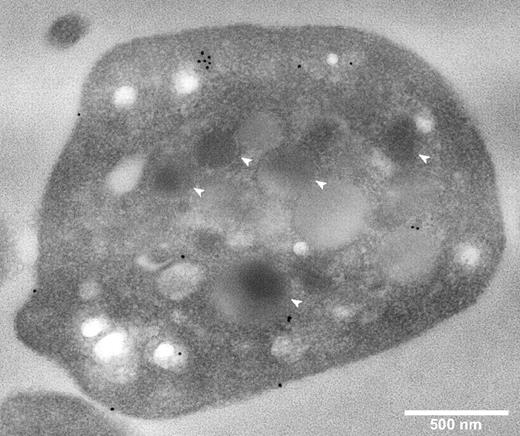

The intracellular localization of CFH in fixed permeabilized platelets was determined by immunostaining and imaging of sections via transmission electron microscopy (TEM), and of whole cells by laser fluorescence spinning disk confocal microscopy. TEM of immunogold-labeled sections (Figure 2) showed CFH-labeled protein distributed around the cell surface and throughout the cytoplasm, with no evident specific association with α-granules or other organelles. A rabbit polyclonal anti–human CFH (SCRs19-20) antibody was used for these experiments and those described in Figure 3; an antibody specific for CFH (SCRs1-4) recognizing the N-terminal region gave the same results (data not shown).

Platelet CFH is distributed throughout the cell and not preferentially localized to α-granules. Thin-section TEMs of representative normal platelets immunogold labeled for CFH (original magnification ×40 000). White bar represents 500 nm; white arrows, α-granules. Primary anti-CFH rabbit polyclonal antibody was detected by immunogold-tagged (10 nm) secondary antibody (black spots). Immunogold-CFH was distributed throughout the cytoplasm with some on the surface but none in recognizable α-granules (compare white arrows with black spots).

The whole-cell distribution of CFH was examined in fixed, permeabilized platelets costained for CFH and other proteins having known intracellular distributions (Figures 3–4). Cells in an unperturbed, resting state were examined as illustrated in Figure 3A where β-actin staining outlines the plate-like shape of cells viewed from the top and side, and Figure 3B where tubulin rings (red) delineate quiescent platelets with intact VWF-containing α-granules (green). These granules were consistent in size and distribution with published images.23 Because previous reports suggested that CFH is localized to platelet α-granules, we first assessed its distribution relative to the known granule-associated proteins VWF (Figure 3C) and fibrinogen (Figure 3D), which are present in 2 distinct populations of α-granules,23 CD63 (Figure 4A), which is present in both dense (δ-) granules and lysosomes, and the lysosomal protein LAMP-1 (Figure 4B). The results show that, unlike these proteins, CFH is not concentrated in granules but rather appears to be present throughout the cytoplasm and possibly on the cell surface (as seen in TEM images; Figure 2). The presence of CFH in these locations is supported by the overlap observed in cells costained for CD61 (GPIIIa, β3 integrin; Figure 4C), found on the cell surface and in the cytoplasm, and the cytoplasmic protein β-actin (Figure 4D). Unpermeabilized platelets showed markedly less CFH staining (data not shown), indicating that much of the protein is inside (washed) cells. These visual impressions were confirmed by the results of whole-cell protein colocalization analysis of representative images (Table 1). Mean values obtained for the Pearson correlation coefficient indicate significant colocalization of CFH with β-actin and CD61, but not with vesicle-associated proteins. The values obtained for the Manders overlap coefficient confirm the strong colocalization of CFH with β-actin and a weaker association with CD61 (for which the value of the overlap coefficient falls below the arbitrary significance limit of 0.7),24 which is nevertheless stronger than the association with any of the other proteins examined. Taken together, both TEM and laser fluorescence confocal microscopy studies indicated that CFH is distributed throughout platelets and to some extent on the cell surface, and is not concentrated in or confined to α-granules or other secretory vesicles.

It has been proposed that CFH is stored in and released from platelet α-granules,19,38 which suggests that CFH is expressed within the platelet lineage by precursor megakaryocytes and/or taken up from plasma. We began our examination of these possibilities by analyzing the protein content of megakaryocytes grown in serum-free suspension culture, normal, and ARC syndrome platelets (Figure 1). We found that, although some platelet CFH appears to originate from endogenous synthesis in megakaryocytes, α-granules are not required for its presence. Direct examination via TEM of CFH in immunogold-labeled sections from normal human platelets (Figure 2) showed CFH distributed on the cell surface and throughout the cytoplasm, with some apparent association with cell membranes but not specifically with α-granules or other recognizable vesicles.